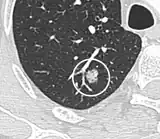

- In case of calcifications, a popcorn-like appearance indicates a hamartoma, which is benign.[3]

- In case of subsolid nodules, being part solid has a higher risk of cancer than being purely ground glass opacity.

Part solid nodule.[9] -

Ground glass opacity nodule.[9]